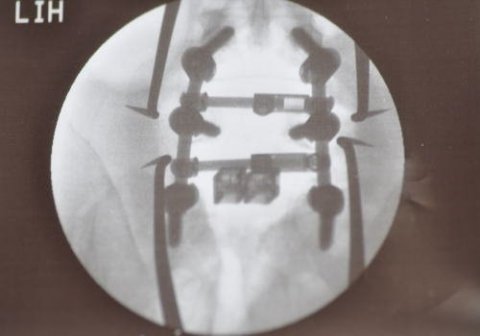

そして、真後ろから撮ったもの。

すごーい!!!

これはもう、ショッカーに改造されたようなもんです。

改造人間誕生です。

そして、真後ろから撮ったもの。

すごーい!!!

これはもう、ショッカーに改造されたようなもんです。

改造人間誕生です。